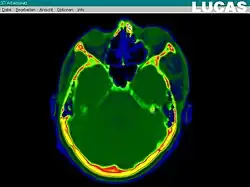

Image gathering ("segmentation") on the LUCAS workstation

The most important component for CAS is the development of an accurate model of the patient. This can be conducted through a number of medical imaging technologies including CT, MRI, x-rays, ultrasound plus many more. For the generation of this model, the anatomical region to be operated has to be scanned and uploaded into the computer system. It is possible to employ a number of scanning methods, with the datasets combined through data fusion techniques. The final objective is the creation of a 3D dataset that reproduces the exact geometrical situation of the normal and pathological tissues and structures of that region. Of the available scanning methods, the CT is preferred,[1] because MRI data sets are known to have volumetric deformations that may lead to inaccuracies. An example data set can include the collection of data compiled with 180 CT slices, that are 1 mm apart, each having 512 by 512 pixels. The contrasts of the 3D dataset (with its tens of millions of pixels) provide the detail of soft vs hard tissue structures, and thus allow a computer to differentiate, and visually separate for a human, the different tissues and structures. The image data taken from a patient will often include intentional landmark features, in order to be able to later realign the virtual dataset against the actual patient during surgery. See patient registration.

Image analysis involves the manipulation of the patients 3D model to extract relevant information from the data. Using the differing contrast levels of the different tissues within the imagery, as examples, a model can be changed to show just hard structures such as bone, or view the flow of arteries and veins through the brain.